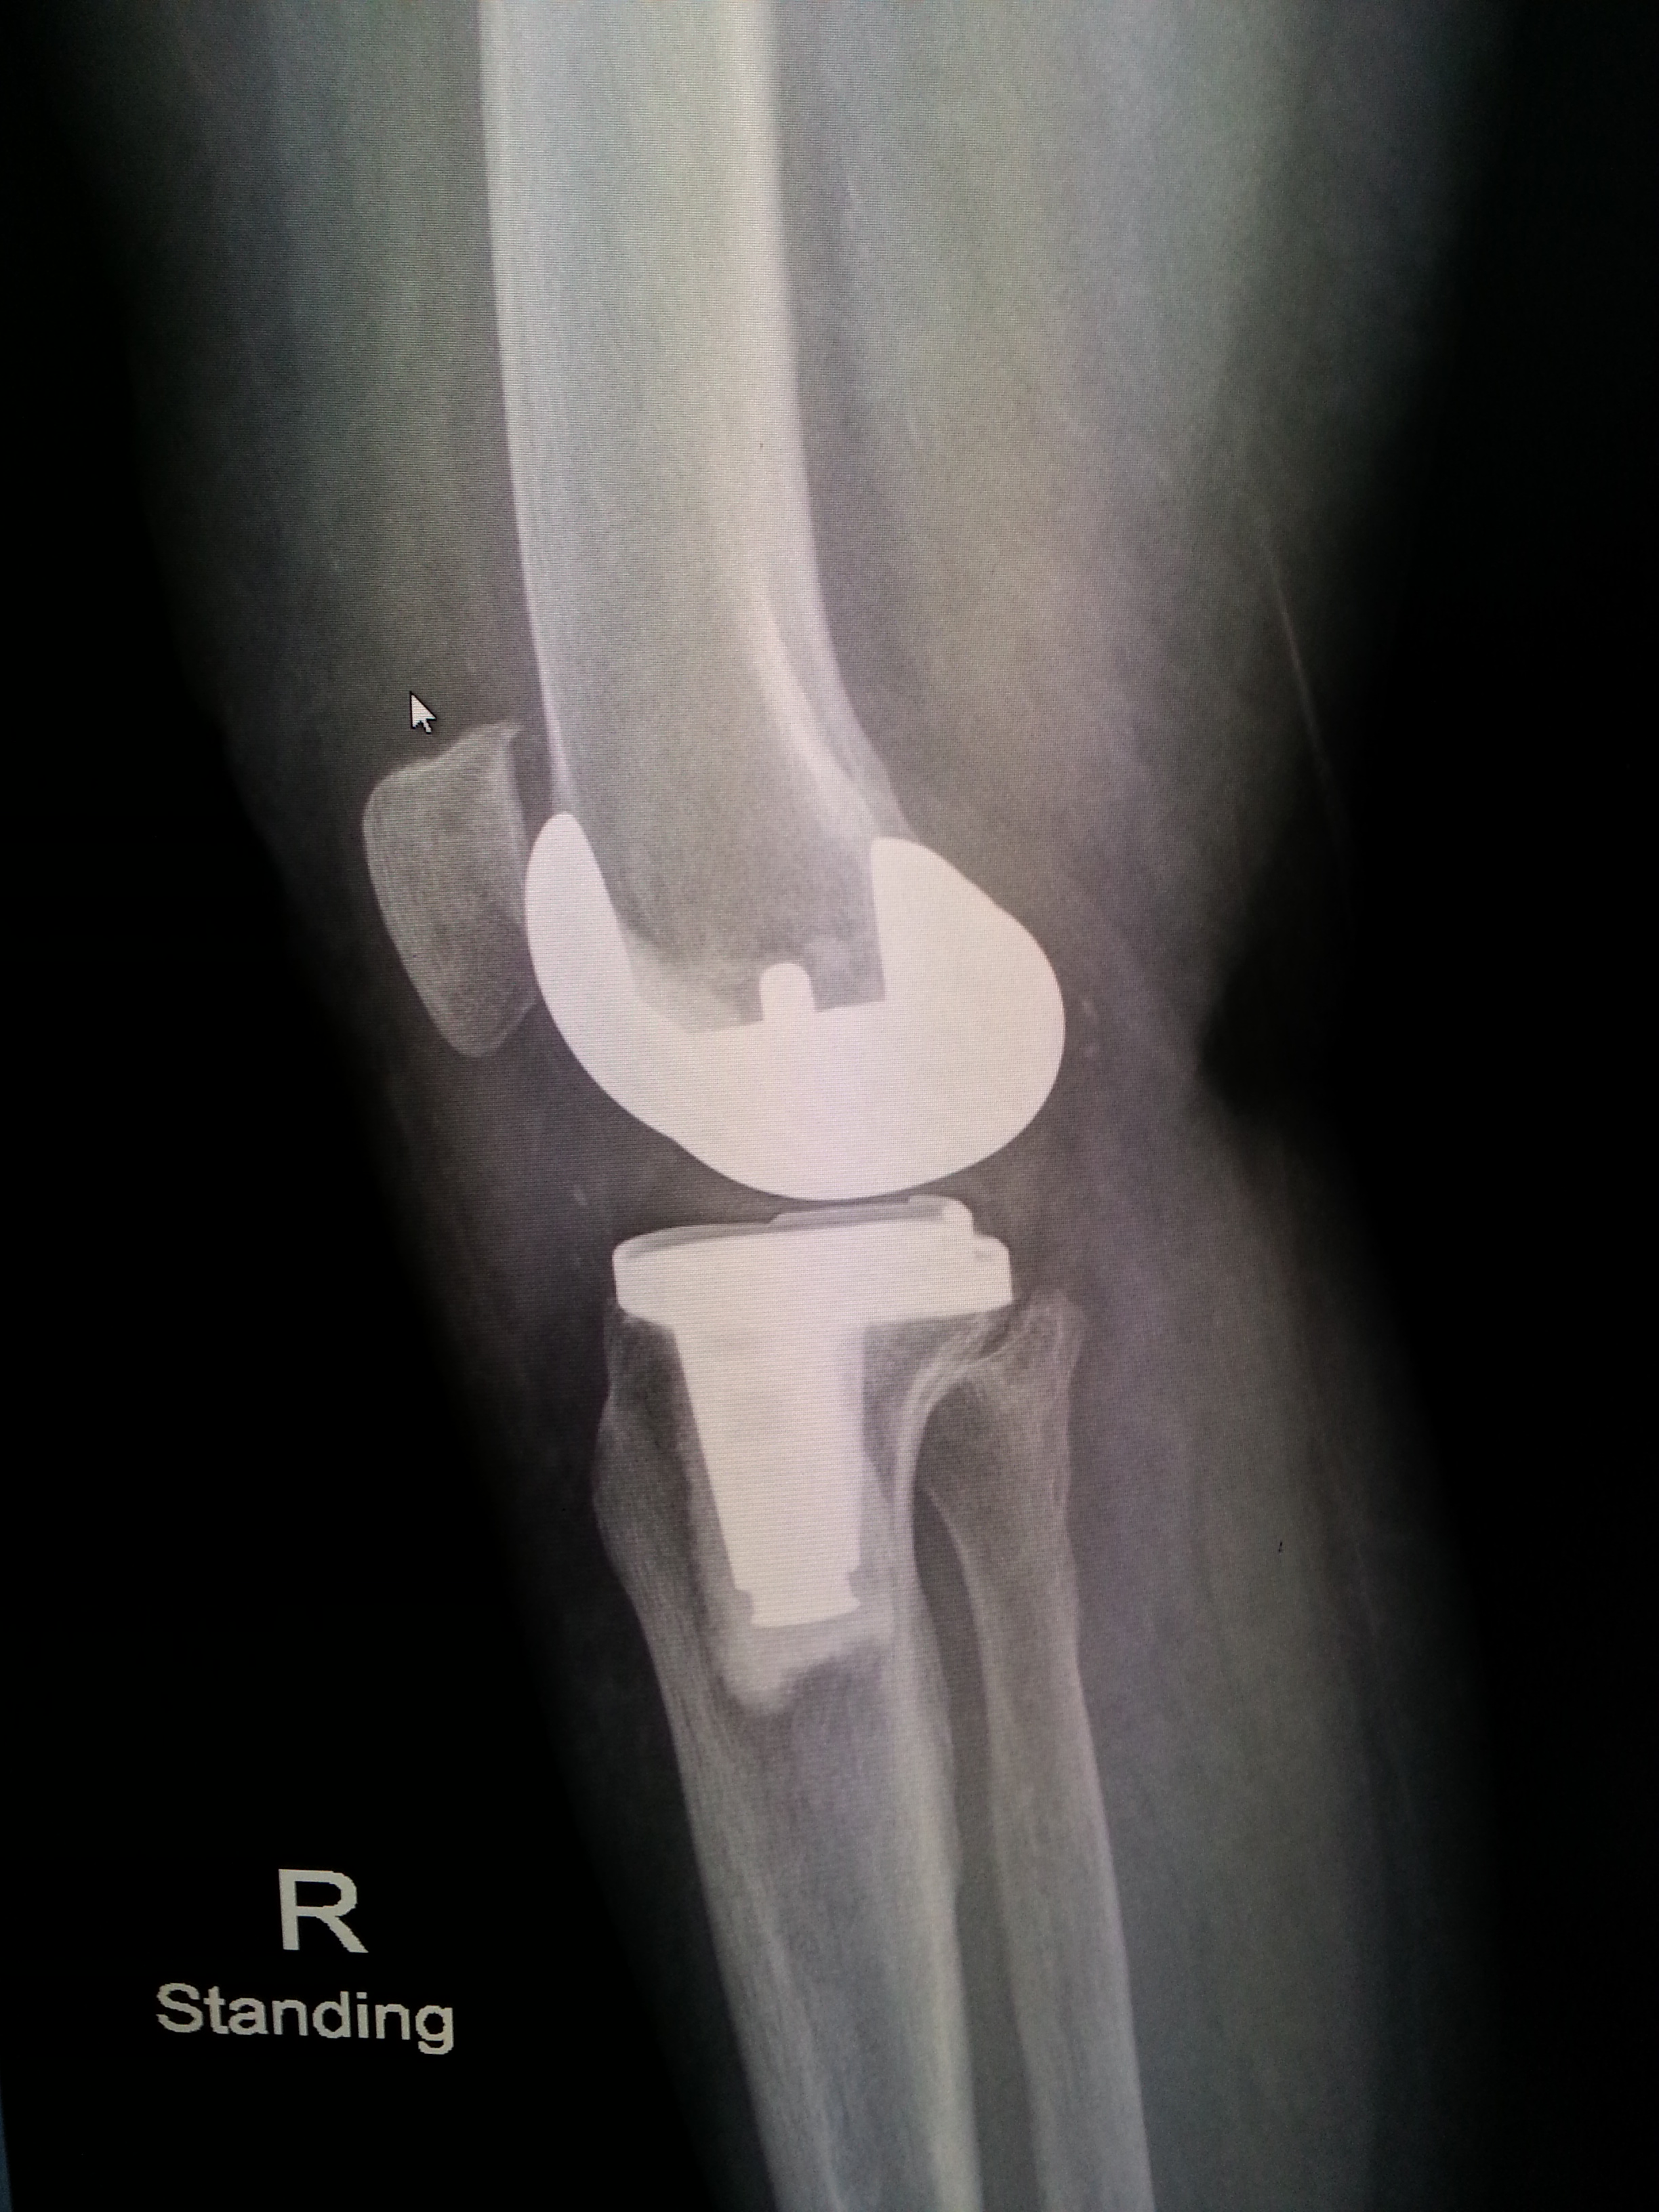

พอไปถึงก็จับเอ็กซ์เรย์ เพื่อรอแผ่นฟิล์มให้คุณหมอตรวจดู อาการเข่าเสื่อมของแม่ ก็พบว่าข้างขวาเสื่อมแน่ ๆ ส่วนข้างซ้าย ก็มีอาการเสื่อมแต่น้อยกว่า ตัดสินใจผ่าทีเดียวทั้งสองข้าง การผ่าตัดมีทั้งเปลี่ยนเฉพาะบางส่วน และเปลี่ยนเต็มข้อ สำหรับของแม่จัดเต็มข้อทั้งสองข้างเลยทีเดียว

ฟิล์มเอ็กซเรย์ก่อน (ภาพซ้าย) และหลัง (ภาพขวา) ของการผ่าตัดข้อเข่าเทียม ส่วนก้อนสีขาว ๆ ของภาพทางขวามือ คือข้อเข่าเทียมที่ใส่เข้าไป

วันนี้คุณหมอนัดตรวจและมี X-Ray สภาพข้อเข่า เช็คการพับงอ ทุกอย่างผ่านไปด้วยดี (ต้องยกผลงานให้คุณหมอเลย เก่งมาก ๆ )

คนไข้รอคิวกันเยอะแยะมากมายเหมือนเดิม นั่งคุยถ่ายทอดประสบการณ์แลกเปลี่ยน ทั้งคนที่มาตรวจกำลังตัดสินใจ คนที่ผ่าแล้ว คนที่อยู่ระหว่างรักษาตัว ค่าใช้จ่ายในการตรวจและ X-Ray วันนี้ 1,420.-